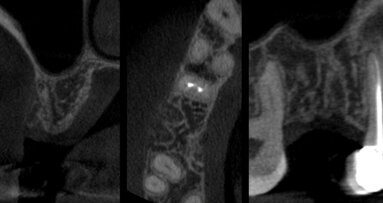

I pazienti sono stati selezionati nell’ambulatorio del Dipartimento di Odontoiatria dell’Ospedale della Versilia, Università degli Studi di Pisa, nel periodo da gennaio 2010 a settembre 2011. Lo studio è stato approvato dal Comitato etico dell’Ospedale della Versilia, Lido di Camaiore (LU). I pazienti inclusi nello studio sono stati selezionati accuratamente, esaminando aspetti clinici e radiografici in ortopantomografia e radiografie endorali; inoltre, sono stati registrati i dati riguardanti età, genere, abitudini viziate (fumo), indicazioni all’estrazione in base a informazioni cliniche e radiografiche, posizione dell’elemento dentario e presenza/assenza del dente adiacente. Dopo la firma del consenso al trattamento, tutti i pazienti sono stati sottoposti ad almeno una seduta di igiene orale prima delle procedure chirurgiche, al fine di predisporre un ambiente orale favorevole alla guarigione.

Tutti i pazienti sono stati sottoposti a estrazione dentaria e intervento di preservazione di cresta al tempo T0; tre mesi dopo l’estrazione, sono stati effettuati i rientri chirurgici in tutti i siti, sono stati prelevati campioni bioptici e sono stati posizionati gli impianti. I siti estrattivi sono stati assegnati in maniera randomizzata al gruppo test (nessun lembo d’accesso e guarigione per seconda intenzione) o al gruppo controllo (sollevamento di un lembo e chiusura per prima intenzione), usando un sistema computerizzato di allocazione random.

A 3 mesi dall’estrazione è stata eseguita la chirurgia di rientro e sono stati posizionati gli impianti (Intralock®, Boca-Raton, Florida, USA) sia nel gruppo test sia nel gruppo controllo. Per raccogliere i campioni nei siti innestati sono state usate frese chirurgiche trephine. Dopo il prelievo dei campioni di tessuto osseo innestato, i siti sono stati preparati secondo le raccomandazioni del produttore (Intralock®, Boca-Raton, Florida, USA). I pazienti hanno ripetuto la terapia antibiotica e antinfiammatoria del primo intervento chirurgico. I campioni prelevati sono stati codificati e inviati per l’analisi istologica al Dipartimento di Scienze mediche orali e Biotecnologie, Università degli Studi di Chieti e Pescara.